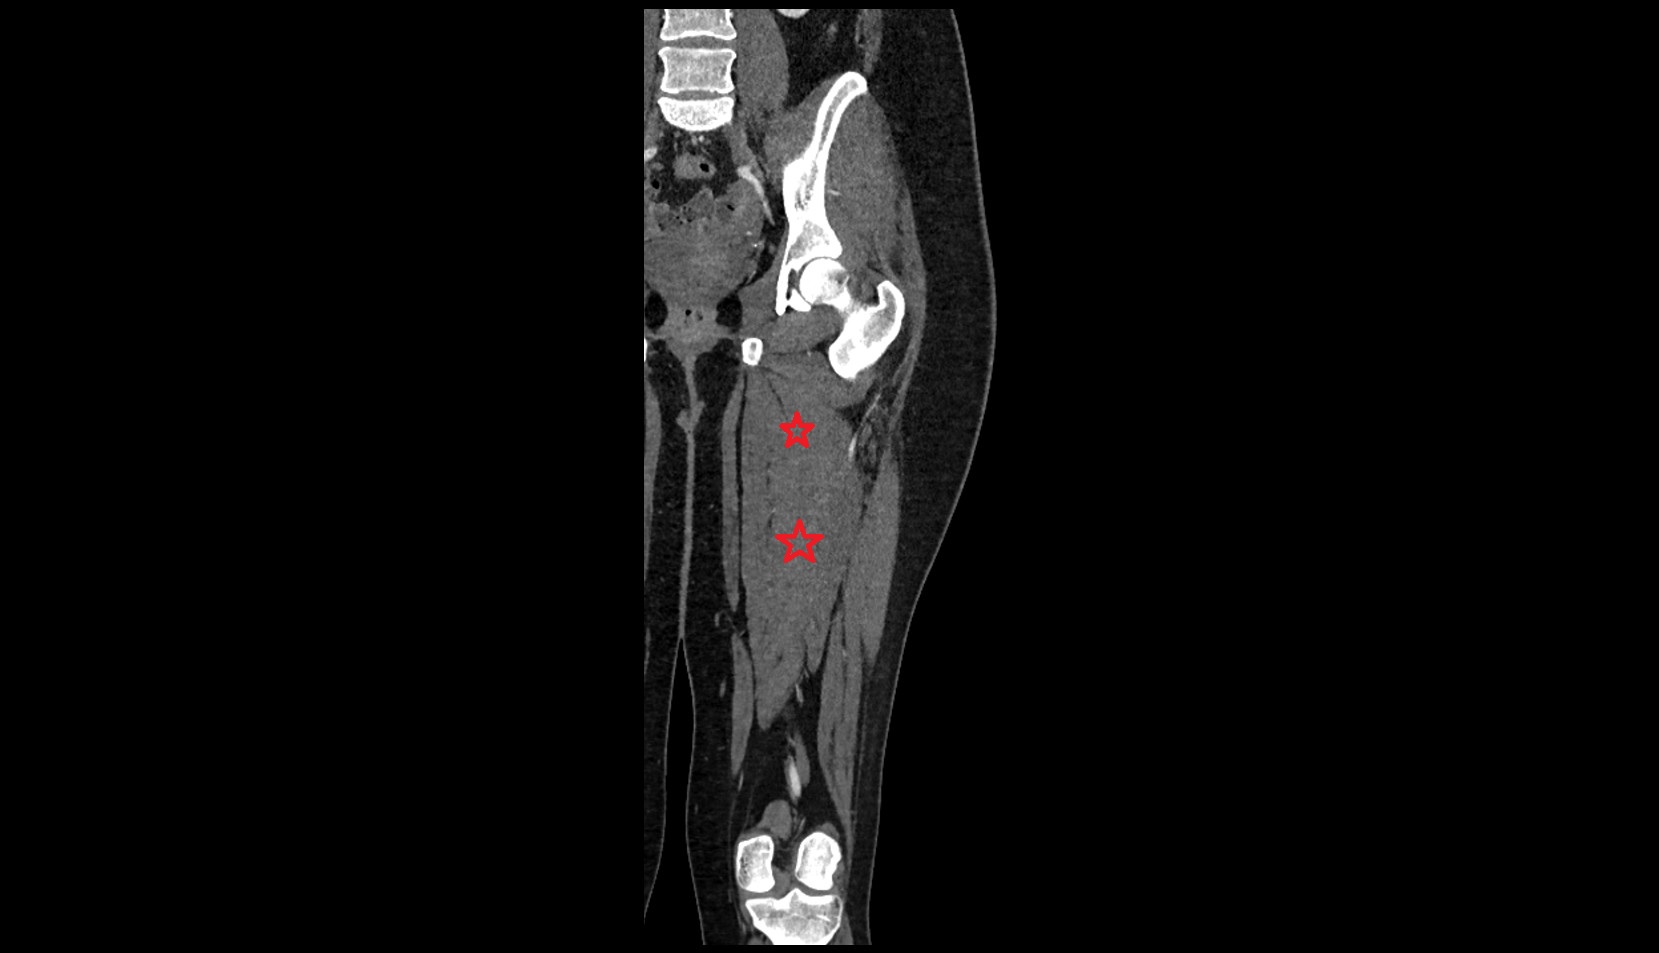

- Deep femoral artery (profunda femoris)

- Femoral artery

- Superficial femoral artery

- Deep femoral vein (profunda femoris vein)